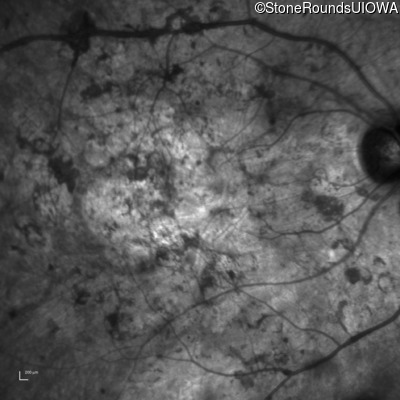

Infrared Fundus Photograph - Right - Hand Motion @ face sc

Exemplar

Infrared Fundus Photograph - Left - Light Perception